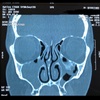

Inflamación de la mucosa de los senos paranasales con presciencia de moco, con la consecuente obliteración de las áreas de paso y drenaje dentro del laberinto anatómico sinusal.

Estudio de imagen que se solicita para sinusitis

Tomografía de nariz y senos paranasales

*Gold standard

En que px se indica la TC para sinusitis

Oncológicos, inmunosuprimidos y sinusitis crónica